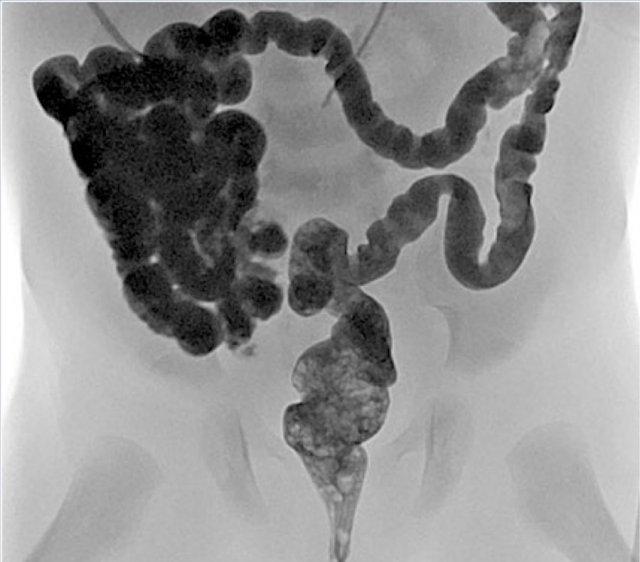

Teo hồi tràng

Tương tự như teo hỗng tràng, teo hồi tràng là hậu quả của một biến cố thiếu máu cục bộ xảy ra trong tử cung.

Có thể tồn tại đồng thời nhiều ổ teo, nhưng đoạn hồi tràng xa là vị trí thường gặp nhất.

Phim X-quang sẽ cho thấy nhiều quai ruột giãn và không có khí trong đại tràng như hình ảnh bên trái.

Thụt tháo đại tràng sẽ thấy hình ảnh đại tràng nhỏ với thuốc cản quang lấp đầy kết thúc dạng túi cùng ở hồi tràng (mũi tên trên hình bên phải).